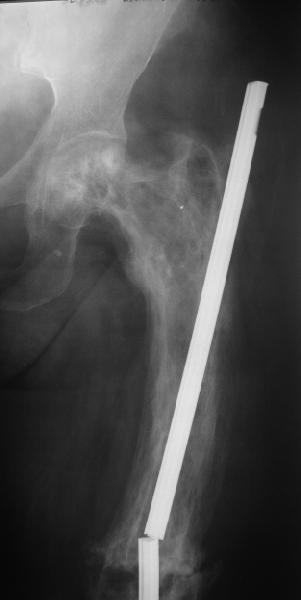

Re: перелом бедра на фоне болезни Педжета

Еще один пример. Пациентка с юга России, прислала рентгенограммы через год. На сегодня прошло 2 г. 8 мес. после операции. Несмотря на не очень убедительный процесс сращения, пациентка ходит. Учитывая остеопороз при Педжете, решили, что динамизировать вообще не нужно.